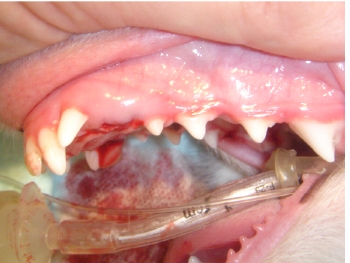

右側観、左側観ともに下顎の犬歯が上顎に刺さっていることがわかります。インクラインプレインという方法で、この下顎の犬歯の角度を変更してみます。

石膏模型を作成し、噛み合わせた時に、下顎犬歯が外側に自然移動するような矯正器具を作成します。

アクリルだけでは強度不足であるために内側にキルシュナーワイヤーを埋め込みます。

実際に取り付けます。

矯正器具を取り外しました。下顎犬歯は左右共に、上顎の歯肉に刺さることなく、外側に移動しております。